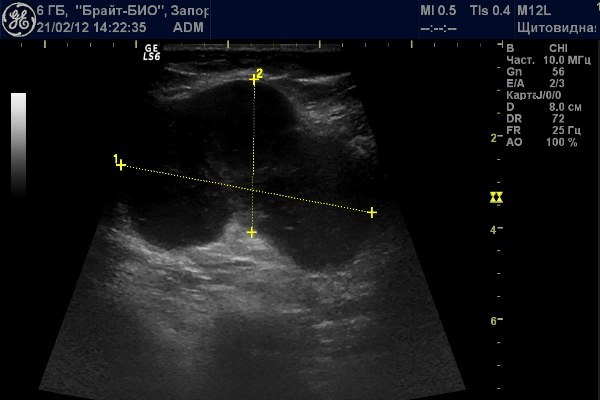

Мезентериальные лимфатические узлы: УЗИ и диагностика